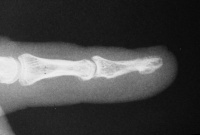

| Two months

following hardware removal. |